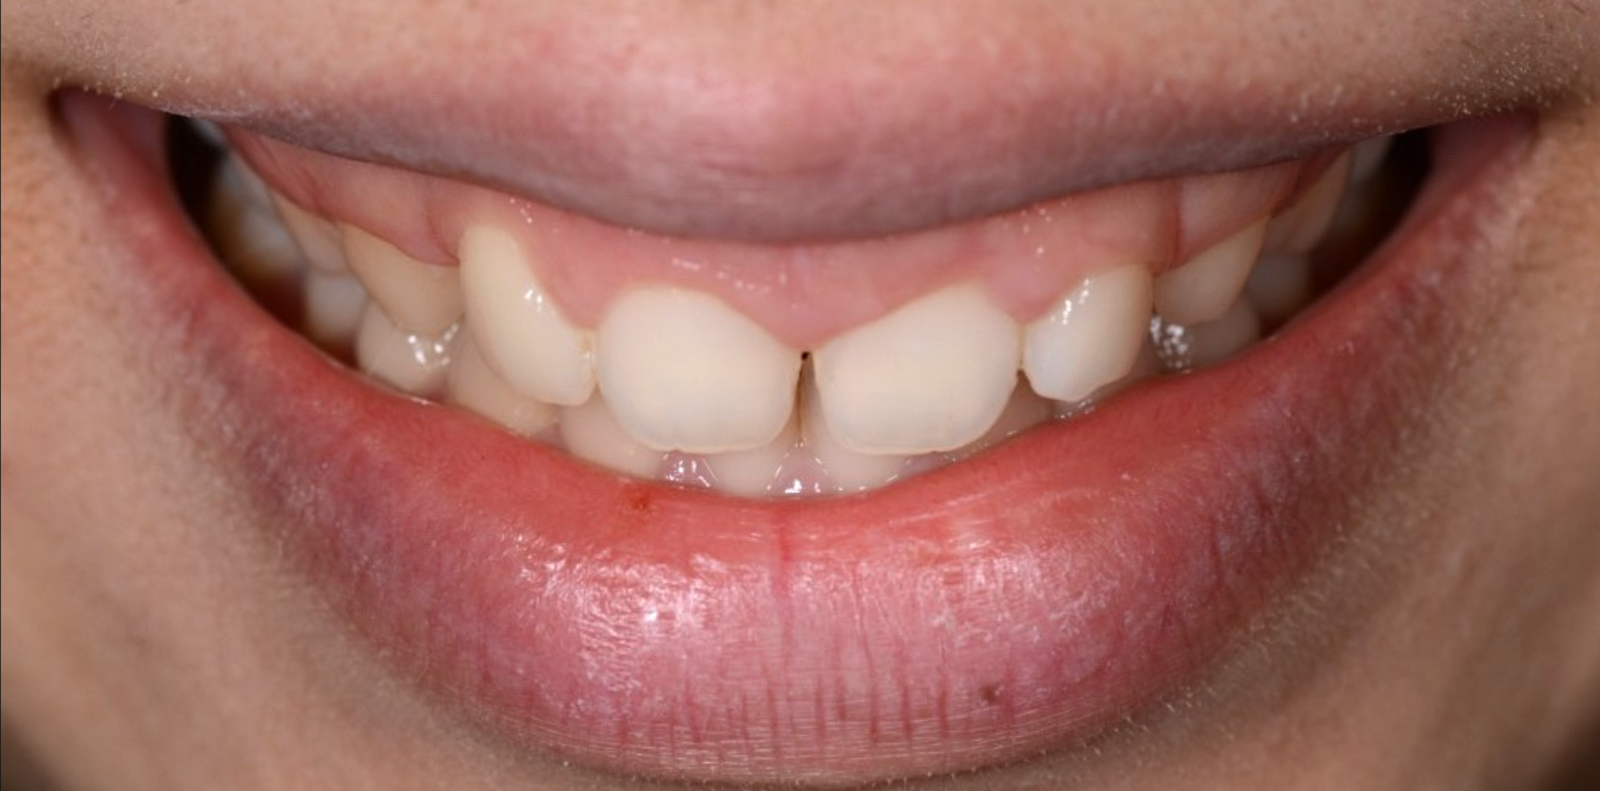

ガミースマイルを歯周形成外科で改善し、笑顔を取り戻した症例

- 年代、性別 30代・女性

- 来院動機 ガミースマイルを治したい

- 治療内容 歯周形成外科